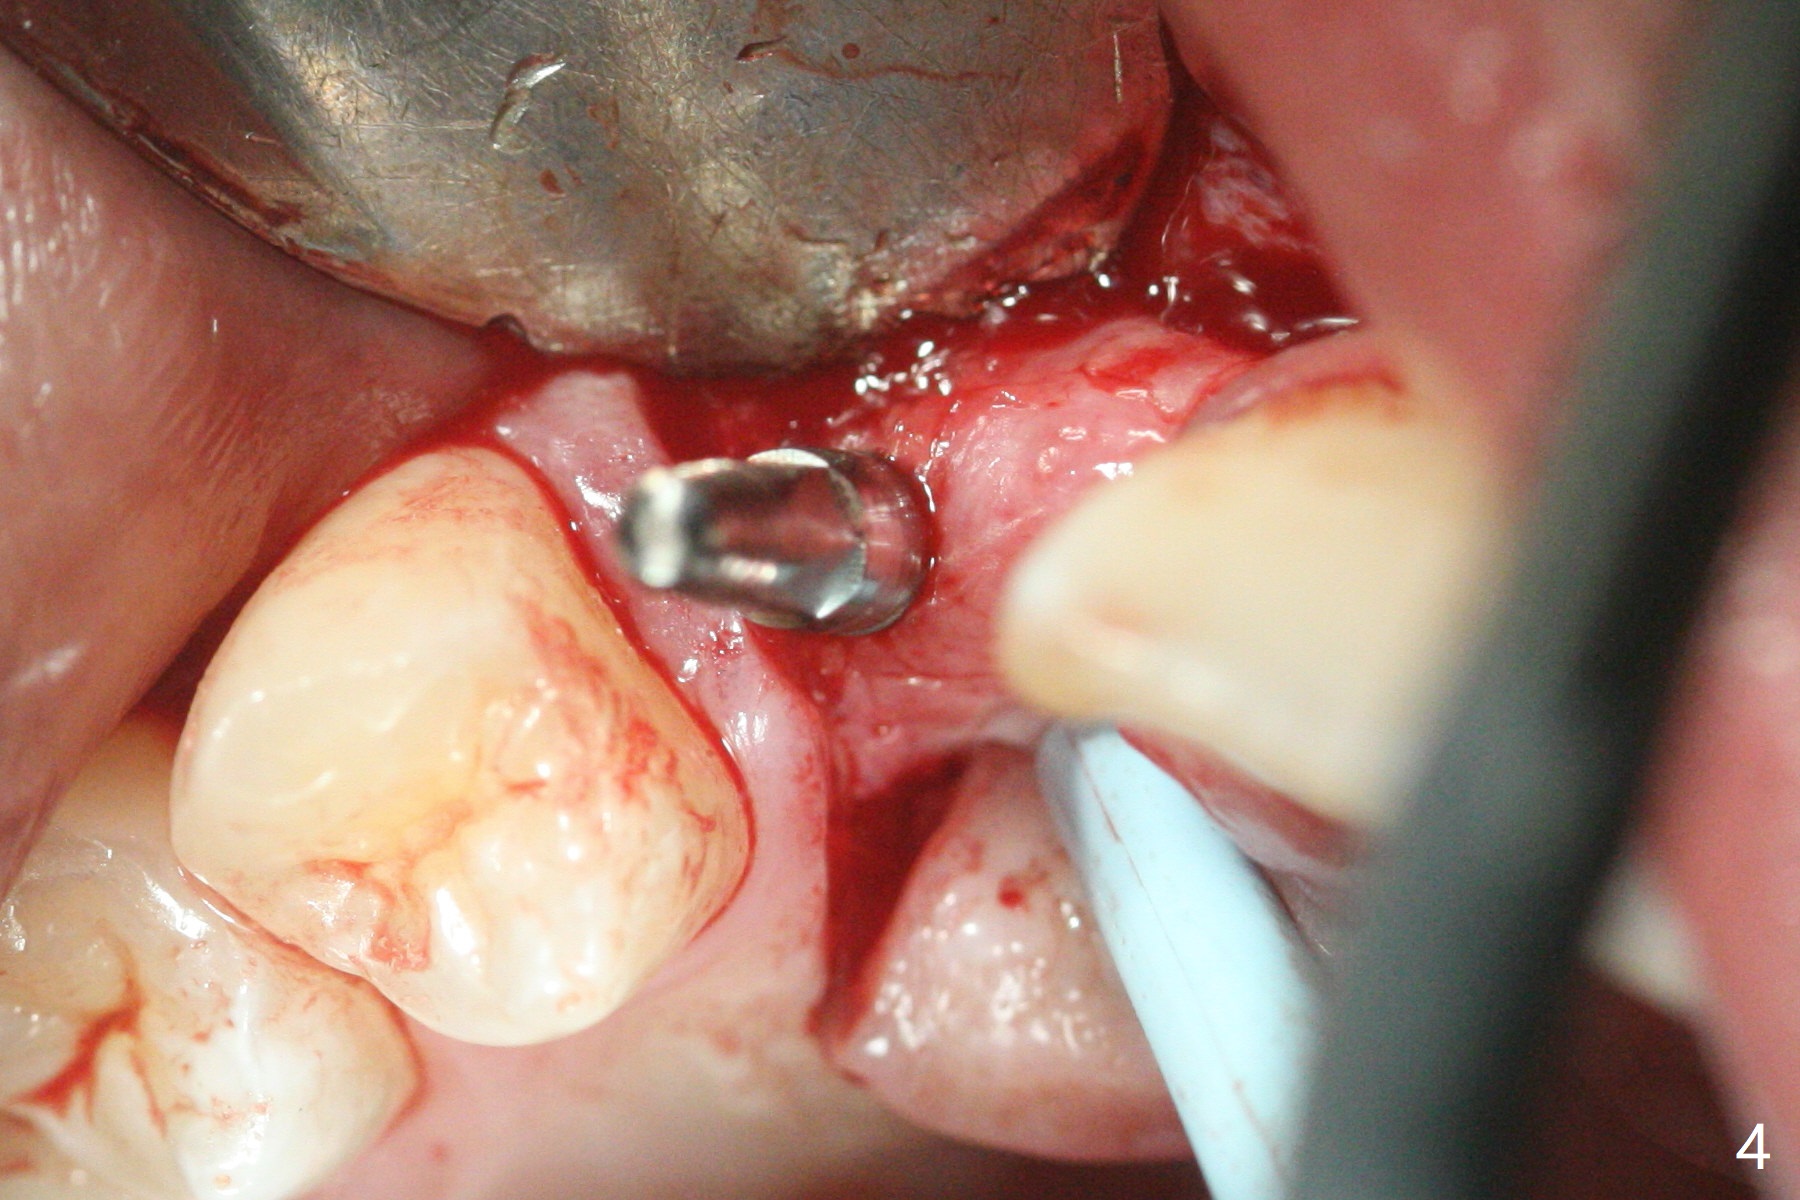

右上尖牙植体拔除,植骨后6个月,切开显示不可吸收膜覆盖的牙槽骨尚饱满(图一),不可吸收膜下面形成一个膜(可能是骨膜,图二:M),在导板指导下,植入3x12(2)毫米一段式植体,颊侧(图三),腭侧(图四)骨下,稍微穿过窦底(图五),植体覆盖粘性骨粉(图六)和PRF膜后,4-0 PGA缝合。伤口有一定张力,使用牙周敷料。术后10天没有疼痛(就没有骨坏死),由于基台存在,牙周敷料没有脱落迹象(图七),也没有撤除。敷料术后13天脱落,伤口好像正常愈合(图八)。由于病人即将回外州上学,提前取模。他喜欢左边牙冠修复形式(牙冠覆盖牙龈),而我们想让牙冠位于牙龈舌侧(图十:T(临时牙冠))。